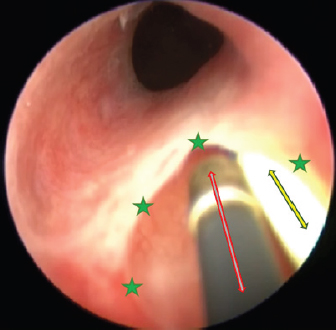

The surgery aimed to cut the outer ureteral membrane and redirect left kidney-produced urine from the urethra to the bladder. Before cutting, a hydrophilic 3 Fr catheter was introduced through a pathologic left ureter opening. It worked as a guide to fully visualize the intramural ureteral tunnel. After that, a Karl Storz monopolar coagulating ball electrode (3 Fr × 53 cm) was introduced through the working channel of the cystoscope sheath. The electrode cut the medial aspect of the ureteral wall up to the bladder trigone, where the contralateral normal ureter opens. The cut membrane did not bleed during the surgery (Figs. 68).

Fig. 6. Cystoscopy picture where the ureteral membrane (see the green stars) is seen before cutting with the semirigid Karl Storz monopolar coagulating ball electrode (marked with a red arrow). A bright yellow 3 Fr guide catheter is seen on the right side of the picture (marked with a yellow arrow).

Fig. 7. Cystoscopy pictures where green stars indicate edges of the cut ureteral membrane. A yellow 3 Fr guide catheter is seen on the right side of both pictures.